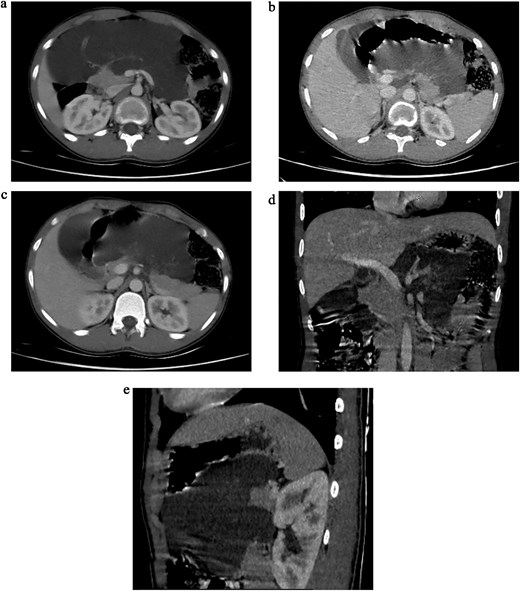

Initial ultrasonography (USS) revealed multiple cystic lesions with parenchymal distortion in the tail of the pancreas. A contrast-enhanced computed tomography (CT) scan showed a large, lobulated, nonenhancing hypodense lesion (6.6 × 16 × 16 cm) with internal septations involving the neck and body of the pancreas. The lesion extended superiorly to the liver hilum and greater curvature of the stomach, anterolaterally to the anterior abdominal wall, and inferiorly to the umbilicus level (L4 vertebra), with no evidence of invasion (Fig. 1a–e). Differential diagnoses included cystic neoplasm and lymphangioma.

(a) Axial sections of CT abdomen (arterial phase) showing cystic mass in relation to pancreas. (b) Axial sections of CT abdomen (arterial phase) showing cystic mass in relation to pancreas. (c) Axial sections of CT abdomen (venous phase) showing cystic mass in relation to pancreas. (d) Coronal section of CT abdomen (venous phase) showing cystic mass in relation to body and tail of the pancreas. (e) Sagittal section of CT abdomen (venous phase) showing cystic mass in relation to body and tail of the pancreas.

In our case, due to logistic limitations, a contrast-enhanced CT (CECT) was performed. It revealed a large, lobulated, nonenhancing lesion involving the neck and body of the pancreas. Typical CECT findings of pancreatic lymphangioma, as described in the literature, include a multilocular, multiseptated, and nonenhancing cystic mass [1, 3].